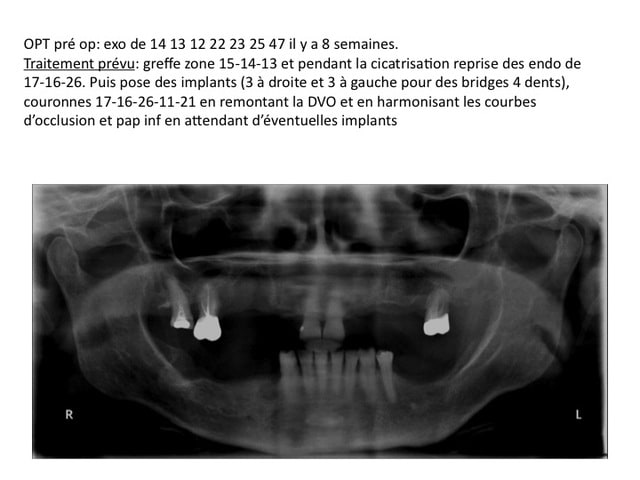

détail des fragments du prélèvement après découpe en 2

Au niveau mésial, le défaut osseux faisait comme une box dans laquelle ma baguette s'adaptait parfaitement. La première vis vient bloquer les deux baguettes et la second vient bloquer la baguette vestibulaire et empêcher tout mouvement.

Mon interrogation c'est plutôt en occlusal, comment éviter une colonisation conjonctive ?